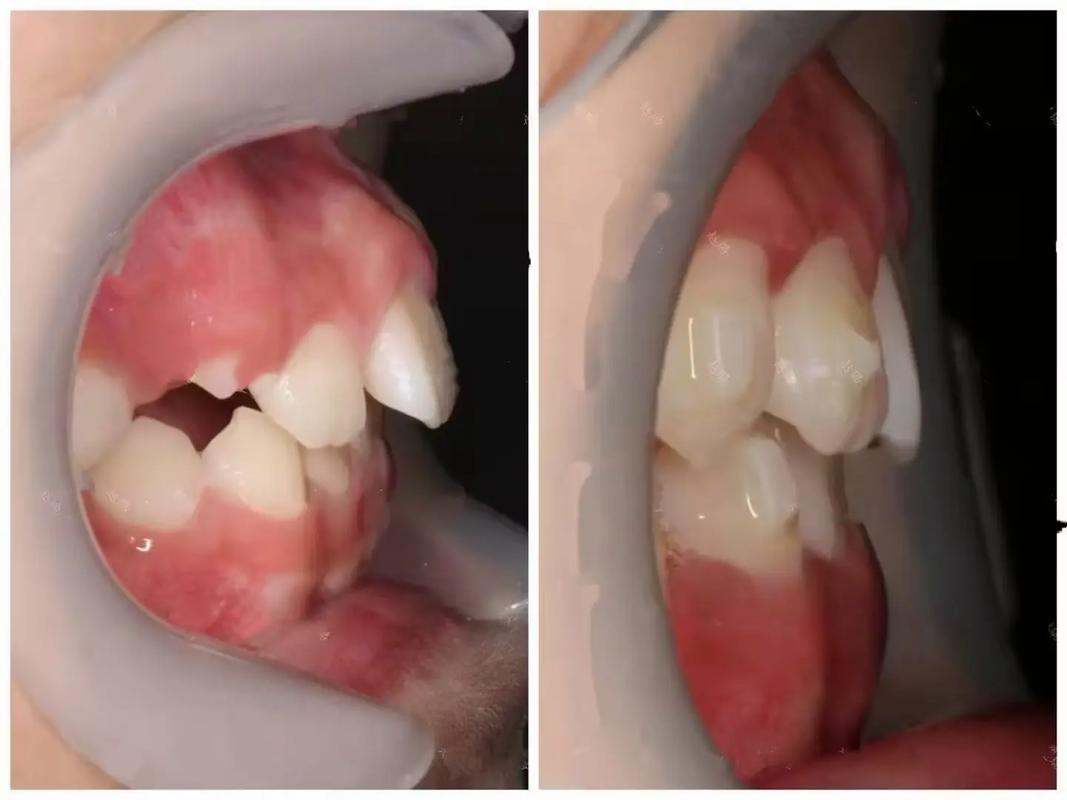

中线是面部中轴线的核心参考,上下中线与面部中线偏差(尤其是>2mm)时,会直接导致面部视觉不对称,中线偏斜时,可能表现为“歪嘴笑”、两侧口角高度不一致、鼻唇沟不对称,甚至加重面部原有畸形(如下颌偏斜),严重影响患者社交中的自信。